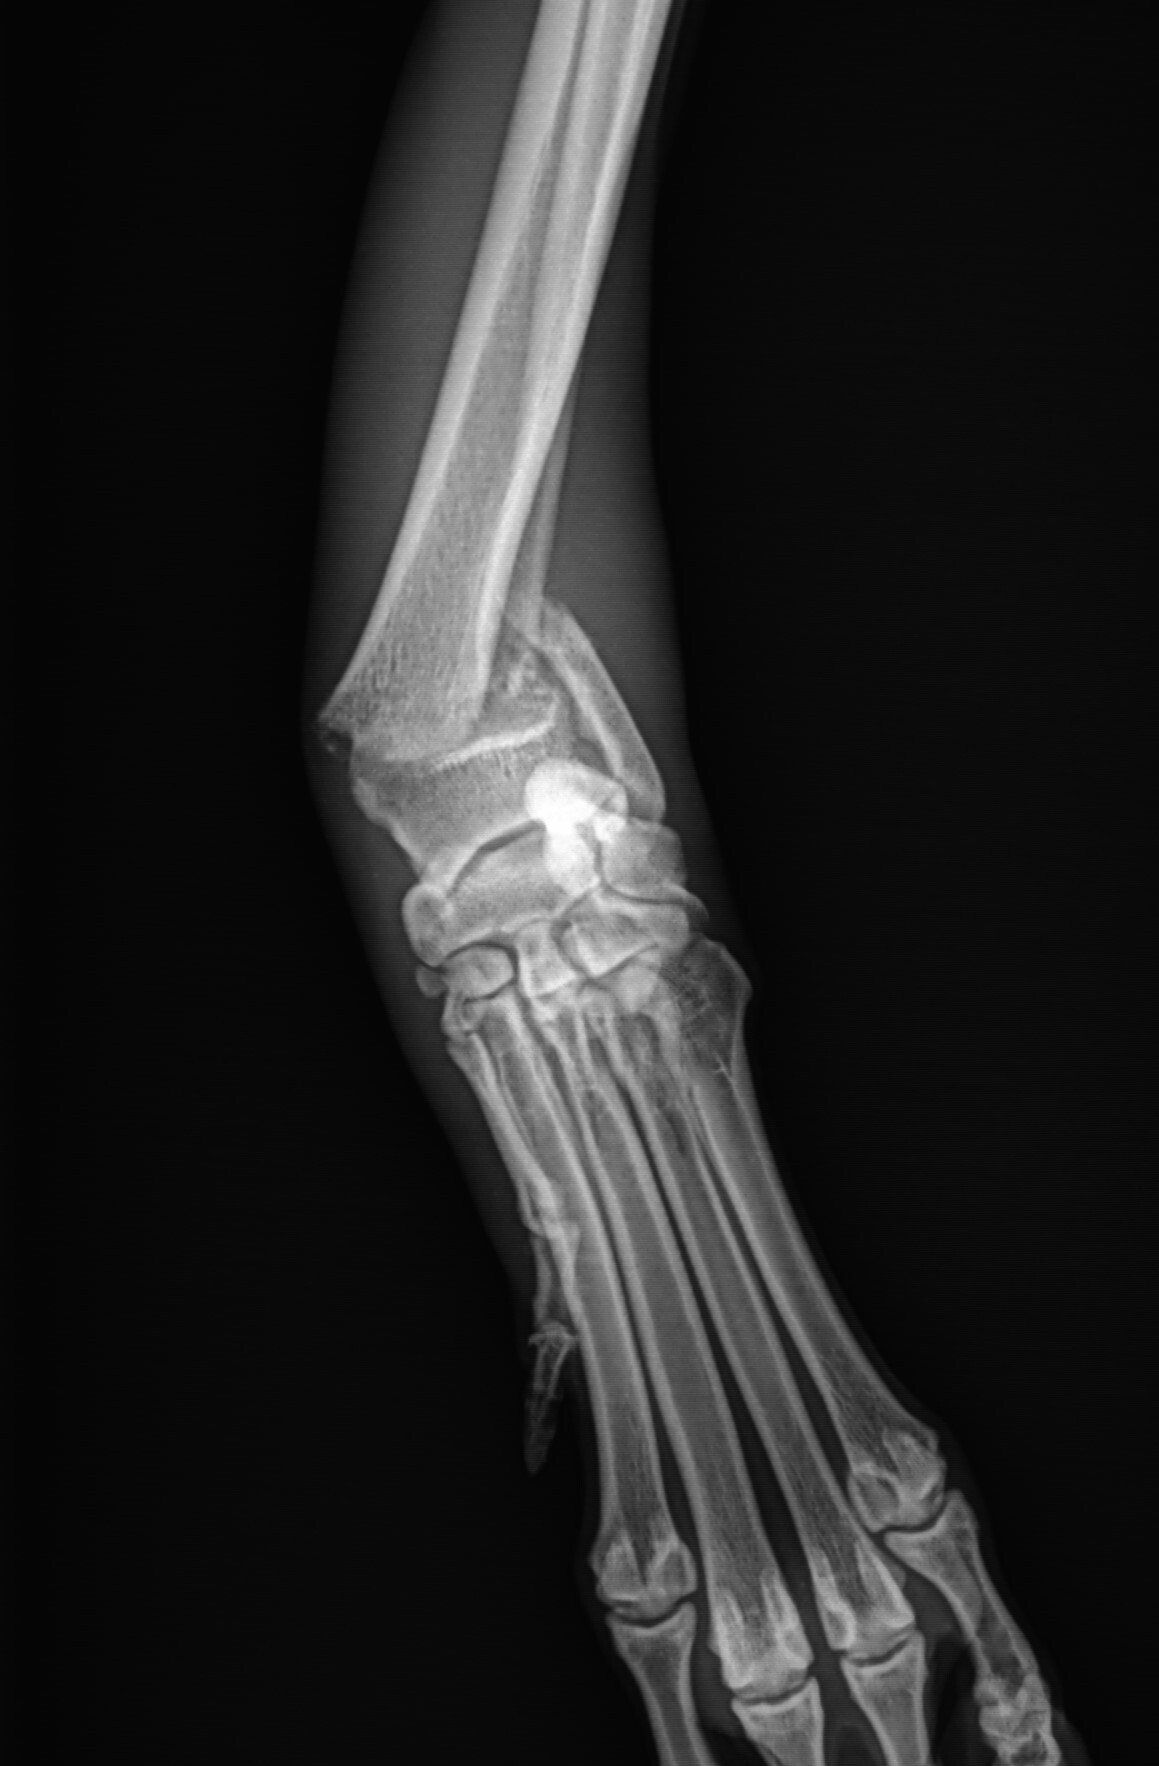

Leg fractures are one of the most common orthopedic problems presented at our clinic and usually result from a traumatic mishap. They can be treated in a variety of ways depending on the location and type of fracture. We can apply a cast to treat certain fractures; however, many fractures will require surgical intervention:

- “Pinning” stabilizes the fracture by inserting a long stainless steel rod into the middle of the bone across the fractured area.

- “Plating” involves attaching a flat stainless steel plate to the bone using screws on either side of the fracture.

Below are x-rays of just a few orthopedic surgeries before and after that Dr. Gose has performed.